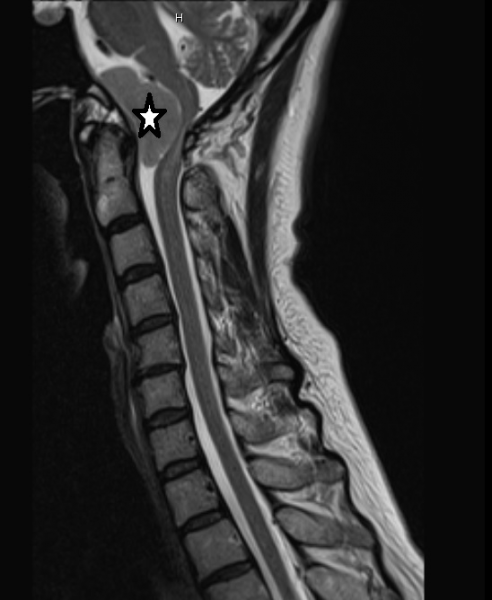

我深入研究了肿瘤的情况后,向法拉坦诚相告:“由于肿瘤的位置难以到达,令手术有所局限,无法100%切除肿瘤,能够切除80%已经很不错了。”法拉表示了解,并勇敢躺上手术台,满心希望开刀后可以恢复正常生活。

手术全程以体感觉诱发电位监督(Somatosensory Evoked Potential,简称SSEP)严密监测,确保不会误伤神经线,在大家的努力下,成功切除80~90%肿瘤,达到预期成果。